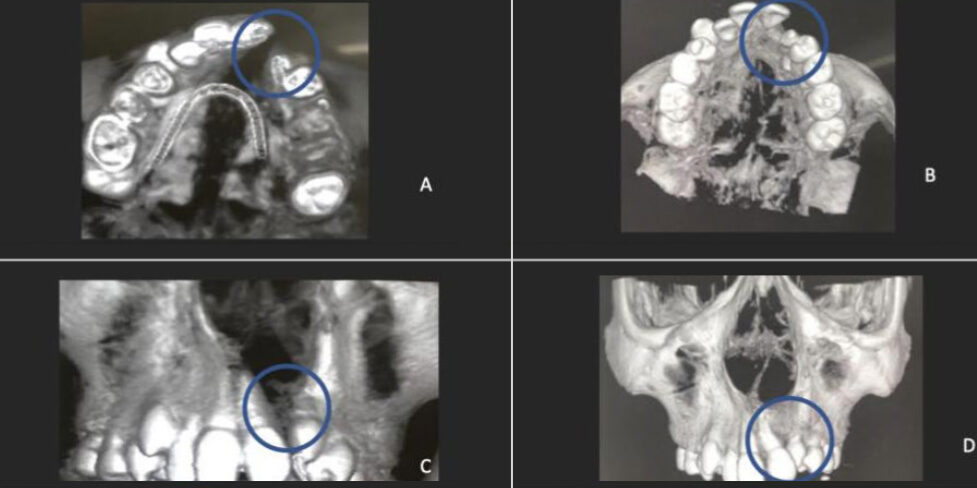

Resultados Promissores e Comparação com Técnicas Convencionais Os resultados obtidos através dessa técnica de bioengenharia, utilizando células-tronco, foram comparados com a abordagem convencional de enxerto ósseo autógeno da crista ilíaca. Tomografias computadorizadas dos pacientes tratados mostram a eficiência do preenchimento progressivo da fissura alveolar, confirmando a não inferioridade da nova técnica. Isso significa que a reconstrução com células-tronco é tão eficaz quanto os enxertos ósseos, porém com vantagens adicionais, como a redução de complicações cirúrgicas.

Quadro ilustrativo com gráfico e tabela

com análise da área do preenchimento

ósseo.

Gráfico e tabela demonstrando

o preenchimento progressivo

da fissura alveolar por osso nos casos

tratados com células tronco e nos

casos tratados com osso autógeno da

crista ilíaca e a não inferioridade da

técnica de bioengenharia de tecido

ósseo em relação ao enxerto ósseo

autógeno de crista ilíaca, demonstrando

a eficiência da utilização das

células tronco de polpa de dentes decíduos

na reconstrução do osso alveolar

de pacientes com fissuras lábio

palatinas.